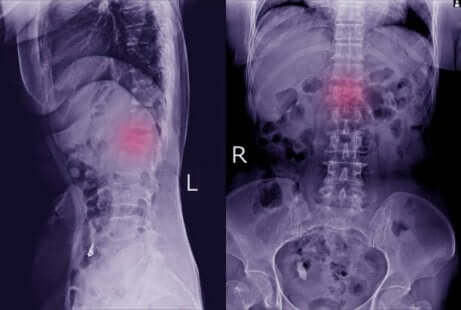

In presenza di queste manifestazioni fisiche, dovremo rivolgerci al medico che confermerà la diagnosi attraverso esami radiologici. Grazie a queste tecniche, è possibile verificare lo spostamento delle vertebre spostate.

In alcuni casi, il medico potrà richiedere esami diagnostici più specifici, come la tomografia computerizzata o la risonanza magnetica. Attraverso tali esami è possibile riscontrare in maniera più chiara la presenza della spondilolistesi e di eventuali danni a carico di ossa e nervi.